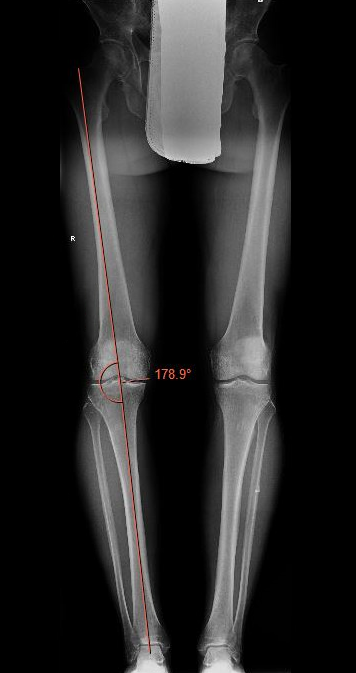

Medial OA

Slight overcorrection into valgus

- anatomical axis 8 - 10o valgus

- mechanical axis 3 - 5o valgus

- Fujisawa point / 62% lateral tibial plateau / lateral tibial spine

Example of medial OA

- anatomical angle 1o valgus

- correct to 8o valgus

- need to correct 7o